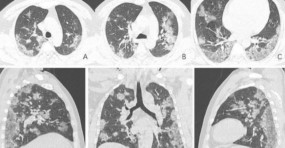

Formation en imagerie COVID

La Société d’imagerie thoracique et la Société Française de Radiologie mettent à disposition régulièrement des cours de formations à l’usage des radiologues et des manipulateurs au fur et à mesure de l’avancée de nos connaissances de cette nouvelle maladie. Vous trouverez au sein des ces cours des informations sur l’épidémiologie de cette infection, sur la place de l’imagerie mais également les différentes mesures de protection au quotidien.